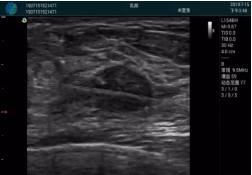

甲狀腺囊性結(jié)節(jié),囊壁鈣化,透聲好

甲狀腺囊性占位

2001年美國健康護(hù)理研究和質(zhì)量監(jiān)督局(AHRQ)批準(zhǔn)了一項(xiàng)關(guān)于提高患者安全性的報(bào)告,建議:在頸內(nèi)靜脈中心置管術(shù)時使用超聲引導(dǎo)。此后超聲引導(dǎo)穿刺被用于幾乎所有的急診穿刺操作,尤其是血管穿刺。

便攜超聲在急診穿刺中的應(yīng)用:

* 提高了穿刺成功率

* 減少了穿刺損傷及并發(fā)癥

* 縮短了操作時間

* 減輕了患者痛苦